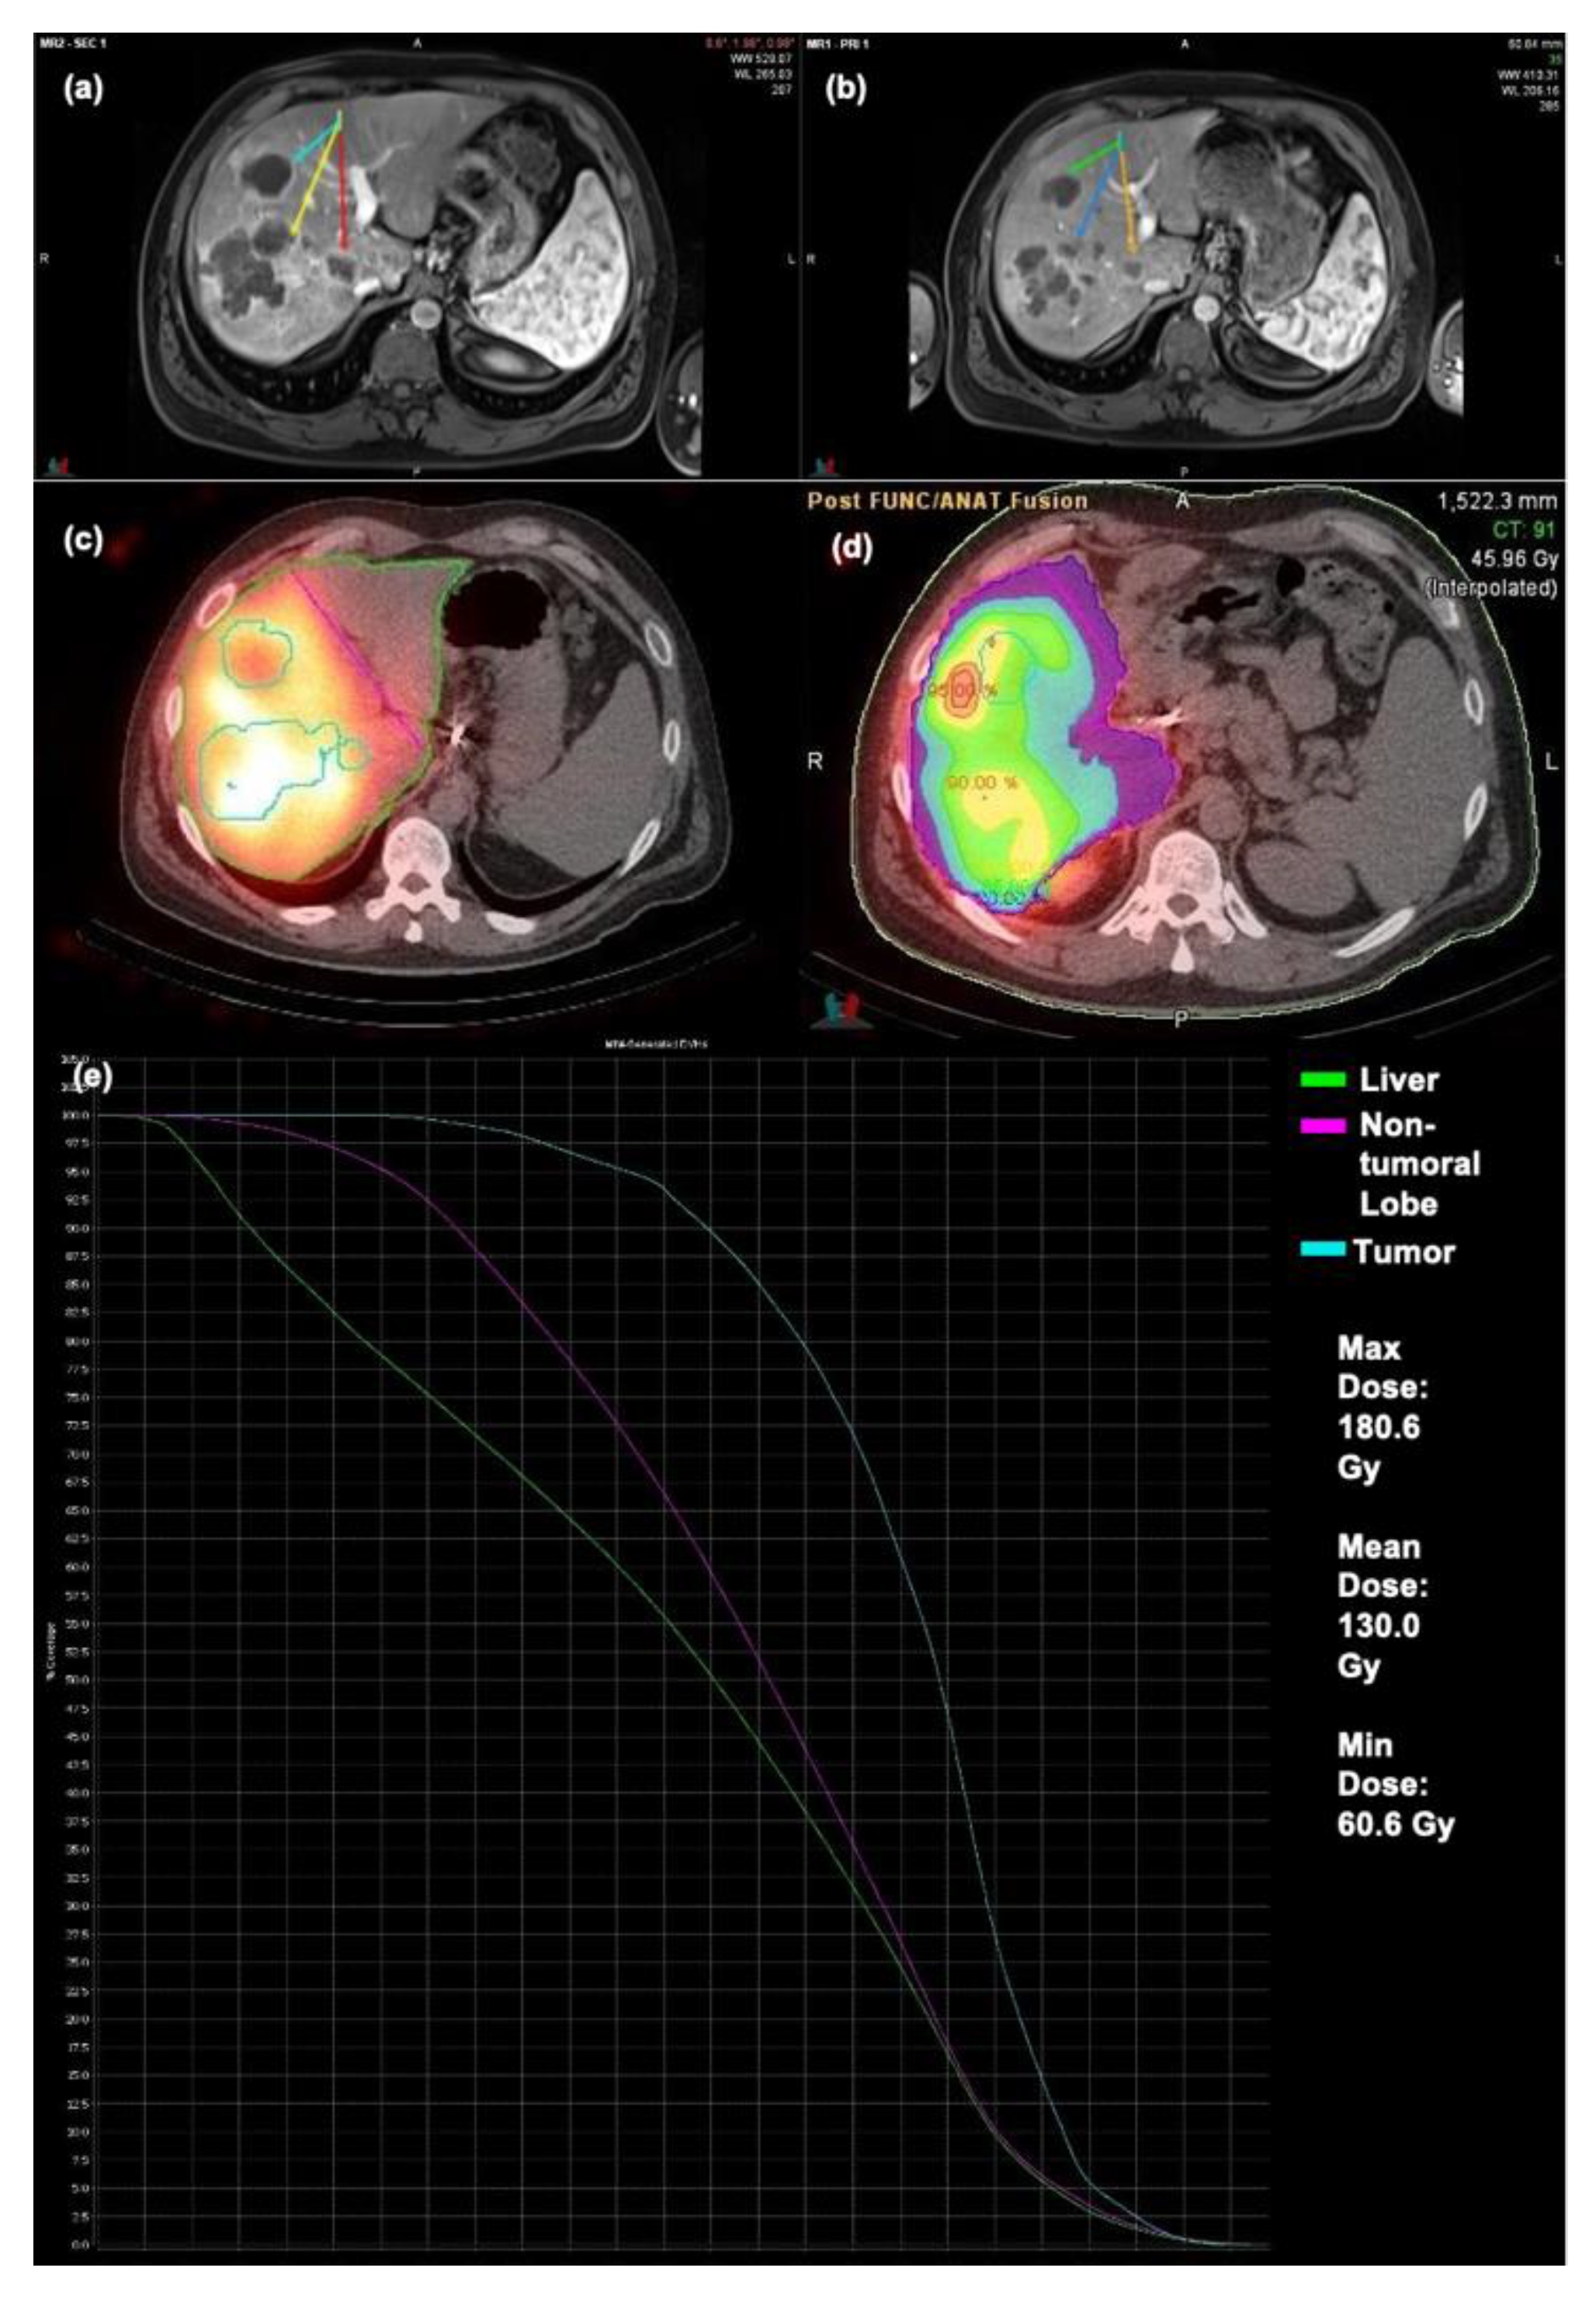

An example of a patient exhibiting OR can be seen in Figure 4. Prescribed activity of 42.8 mCi of resin microspheres was administered to the patient’s replaced right hepatic artery. Follow-up MRI demonstrated a partial response to treatment for the treated lobe. Treated lesions in this case had a mean TD of 130.0 Gy, a maximum TD of 180.6 Gy, and a minimum TD of 60.6 Gy.

Figure 4.

Patient exhibiting OR to Y90 therapy (a) Pre-op MRI (b) Post-op MRI (c) Bremsstrahlung SPECT/CT (d) Dosimetry map (e) DVH Curve.